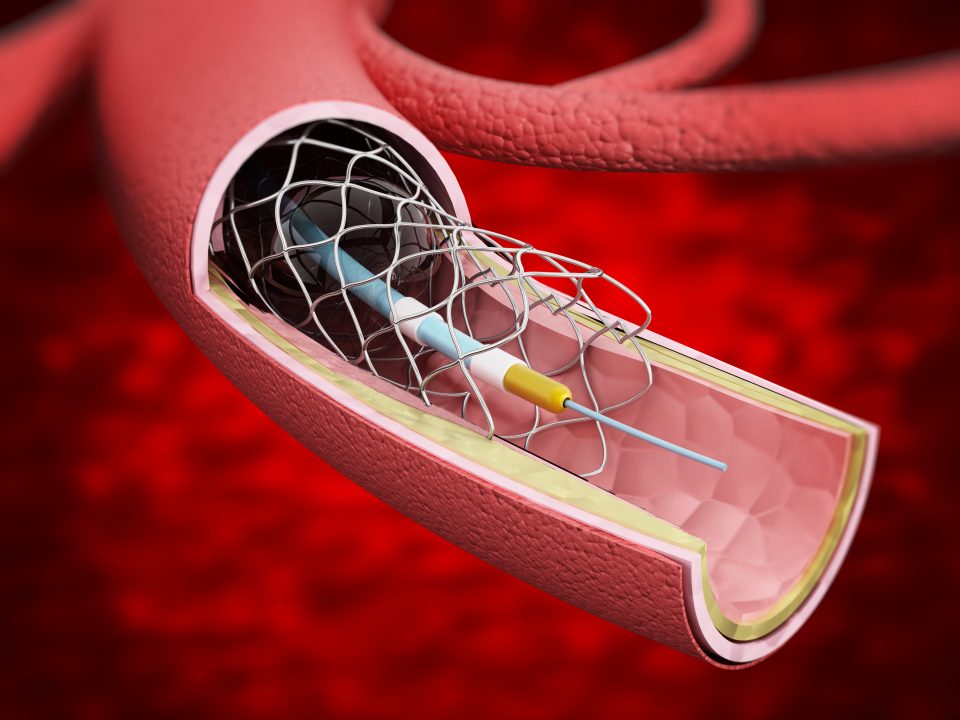

stent

A novel NanoCoated Coronary Stent (NCS) failed to meet noninferiority criteria to a drug eluting stent, new trial ...

Discontinuation of aspirin at 90 days following stenting and continuing on P2Y12 inhibitor monotherapy, was not ...

The Absorb bioresorbable vascular scaffold was shown to be noninferior to the Xience Cobalt ...

A novel polymer-free amphilimus-eluting stent was found to be safe and efficacious compared to the latest-generation ...

A polymer-coated zotarolimus-eluting stent (Resolute Onyx) with a novel thin-strut metallic platform demonstrated ...

Ultra-thin strut drug-eluting stents (DES) may promote better clinical outcomes than thicker strut second-generation DES ...